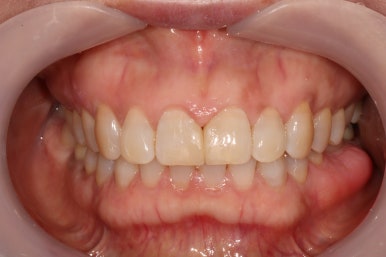

정면에서 본 사진입니다.

잘 모르실 수도 있겠지만, 잇몸이 염증이 생겨 치주염으로 인해 빨갛게 변하신 것을 보실 수 있어요.

즉, 잇몸질환-만성치주염을 갖고 계신 상태였죠.

위 앞니 (중절치)는 치아 사이 틈을 메우기 위해 예전에 레진치료를 받으신 상태였는데, 치료받으신지 오래되어 레진 충전물의 색이 변하고 어색한 모양을 띄고 있습니다.

앞면, 양쪽 옆면 모두 아주 깔끔하게 유지되고 있네요!

기억하고 있으실지 모르겠지만, 전반적으로 나타내고 있던 잇몸의 붉은색도 대부분 사라져 있는 상태입니다.